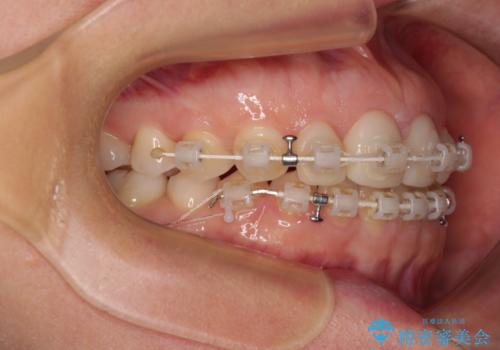

- 大きすぎる上顎前歯と、隙間の空いた下顎歯列を気にして来院された患者様です。

上顎前歯にはセラミッククラウンが装着されており、顔や他の歯と比較して幅の大きい状態でした。

下顎前歯は空隙歯列弓であったので、アンカースクリューとワイヤー装置を用いてスペースを閉じていくこととし、上顎前歯は矯正治療用の仮歯に置き換えた上で、仮歯の大きさを削って小さくしながら、上下前歯部の部分矯正を行うこととしました。